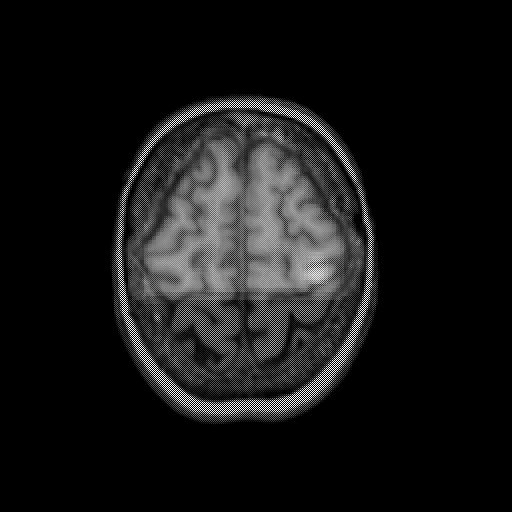

overlay: Slice 43

Slice 43

MRCBFCBF with

T1PDT2T1PDT2